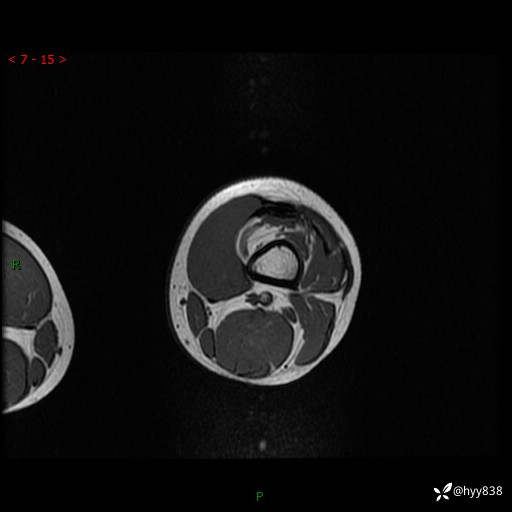

左大腿MRI平扫+增强